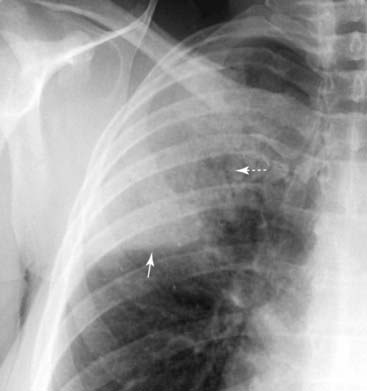

Figure 3-4 Silhouette sign, right middle lobe pneumonia.

A, Fluffy, indistinctly marginated airspace disease is seen to the right of the heart. It obscures the right heart border (solid black arrow) but not the right hemidiaphragm (dotted black arrow). This is called the silhouette sign and establishes that the disease (1) is in contact with the right heart border (which lies anteriorly in the chest) and (2) is the same radiographic density as the heart (fluid or soft tissue). Pneumonia fills the airspaces with an inflammatory exudate of fluid density. B, The area of the consolidation is indeed anterior, located in the right middle lobe, which is bound by the major fissure below (dotted white arrow) and the minor fissure above (solid white arrow).